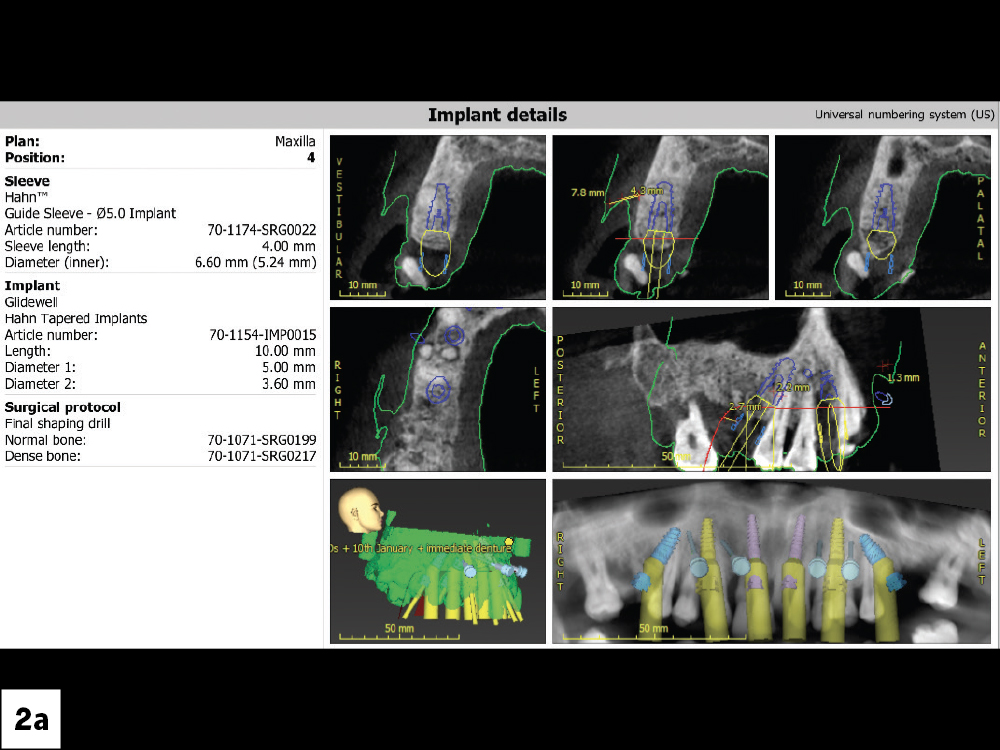

After reviewing the patient’s health history and finding no contraindications to the treatment plan, the next step was evaluating the bone volume available to support the implants.

The case was planned preoperatively through the digital treatment planning (DTP) process, working with the DTP team at Glidewell.

Figures 2a, 2b: After reviewing the patient’s health history and finding no contraindications to the treatment plan, the next step was evaluating the bone volume available to support the implants.

The case was planned preoperatively through the digital treatment planning (DTP) process, working with the DTP team at Glidewell.  This method provides the ability to plan the case from extraction, bone reduction, and implant placement, all the way through to the provisional and final restorations. Through a series of stackable guides, each step is fully guided to ensure the safety of the patient and the most precise outcome.